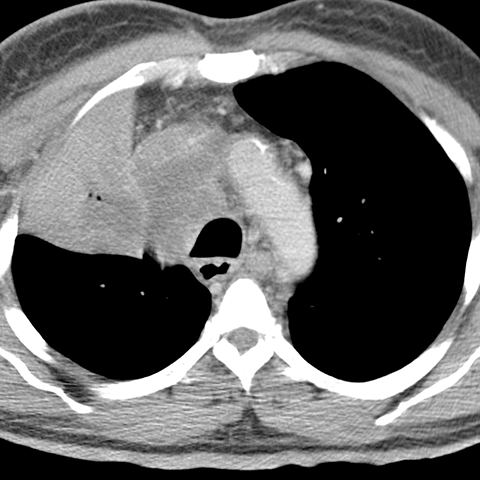

RUL Atelectasis, Consolidation and Cancer [3 of 3]